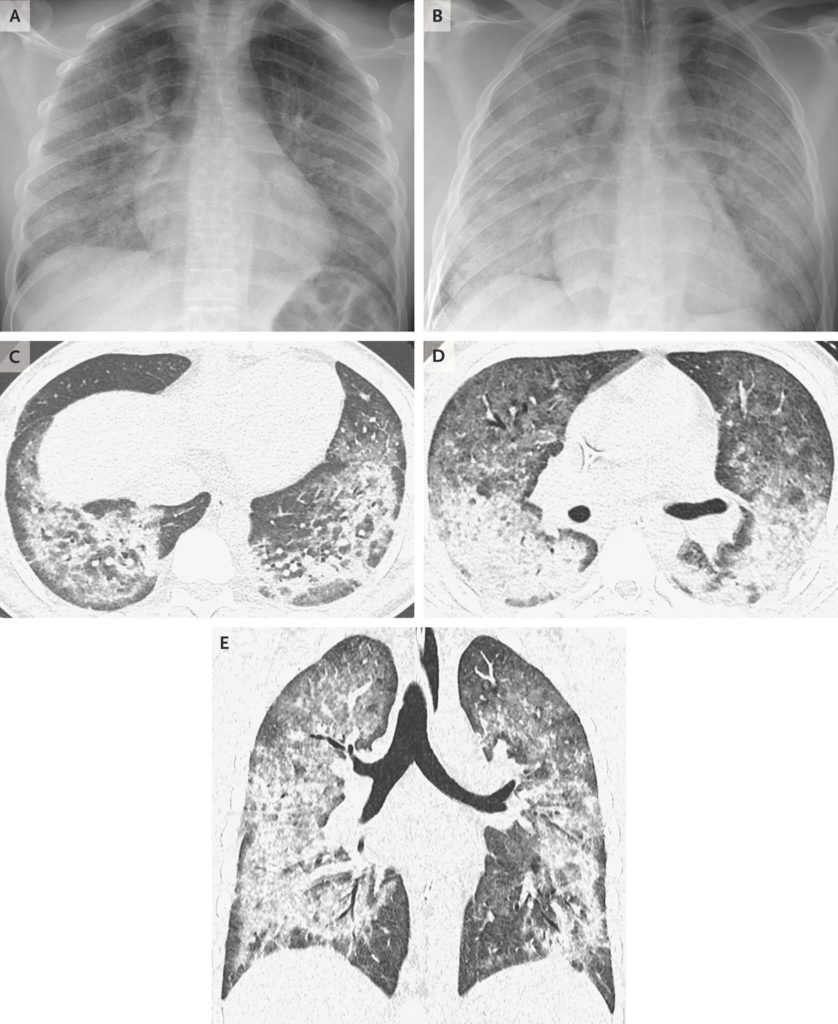

■ すべての患者は、胸部画像検査(症例定義の一部)において、両側に浸潤を認めた。

論文より引用。17歳の症例の肺画像写真。